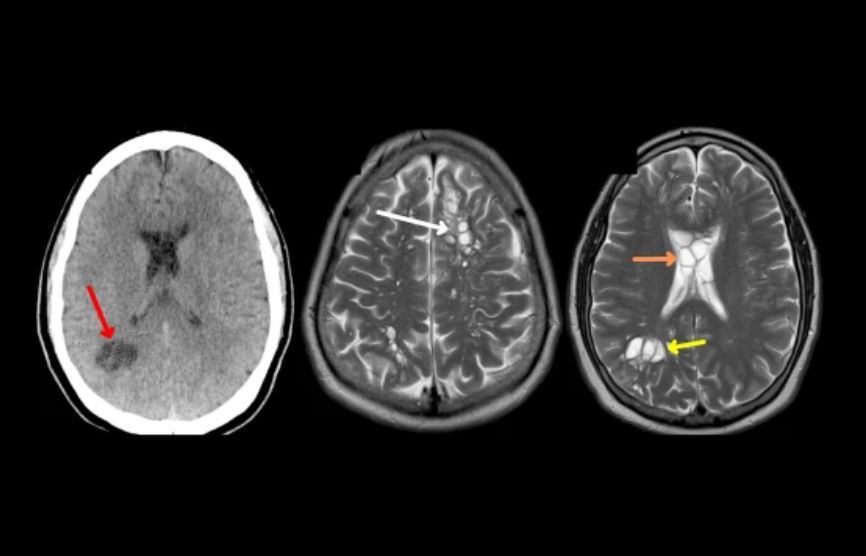

Una tomografía revela numerosos focos quísticos, sacos llenos de líquido en el cerebro del oaciente. | Foto: Eamonn Byrnes et all

El paciente ingresó en el hospital para someterse a pruebas. Una tomografía computarizada reveló numerosos focos quísticos, o sea, sacos llenos de líquido en el cerebro. Las pruebas de anticuerpos dieron positivo a quistes de cisticercosis, y el hombre fue diagnosticado con neurocisticercosis.